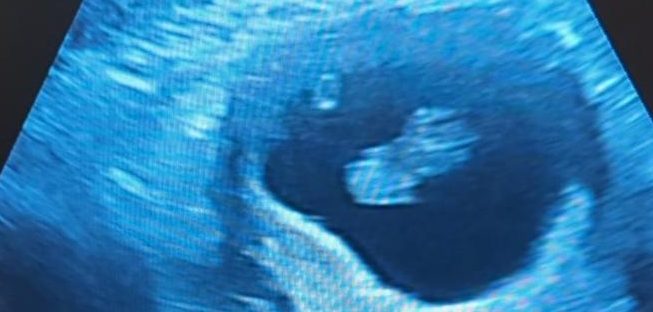

Sure enough, no news came. Tony was required by work to attend a site trip, so I drove myself back to the clinic and checked in, waiting with the same group of women I had five days prior. When it was my turn, I was taken back into the same room and told that we had a 4AB graded embryo. I don’t know all of the details of what that means, but it’s about the second best grading you can have, so that was good news. A catheter was placed through my cervix and into my uterus and presto, the embryo was in and the transfer was complete.